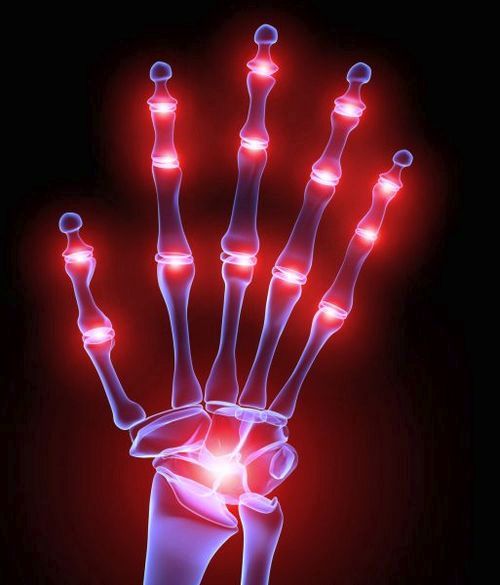

Кисть руки сама по собі складний і тонкий інструмент людського організму і частіше за інших його частин схильна до різних трамвая, інфекційних захворювань, патологічних змін і ушкоджень, які провокують розвиток артриту рук. Найчастіше захворювання вражає дрібні зчленування пальців.

Хвороба розвивається поетапно. Спочатку виникає запальна біль, що підсилюється при спробі рухатися. Після цього навколосуглобових тканини починають запалюватися, а сам суглоб - міняти зовнішній вигляд (напухає і стає гарячим, з'являються почервоніння і невеликі припухлості).

У першому випадку хвороба вражає дрібні суглоби і сполучні тканини. Явна ознака - симетричність ураження (якщо на правій руці виявлено запалення, то воно також проявиться і на лівій), деформація пальців, які набувають веретеноподібну форму.